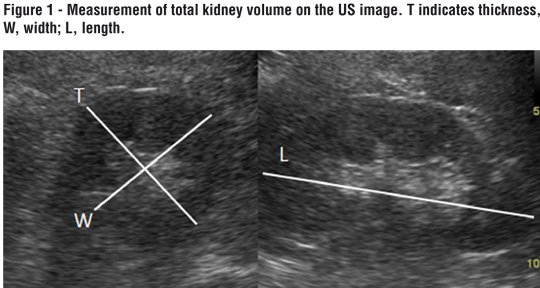

A systematic abdominal sonographic examination (4.5-5 MHz convex array transducer, Aloka alfa 6, Japan) was performed on all patients. The examination was performed with the subject in a supine and prone positions. Kidney measurements were obtained with the subject prone. Kidney length, width and thickness were measured using US. Kidney volume (total volume (Figure-1) and sinus volume (Figure-2)): lenght x thickness x width x 0.523 (5) were obtained. Parenchymal volume was calculated as total volume- sinus volume. RI was calculated automatically by Doppler US (Figure-3).